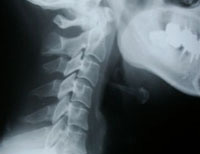

- レントゲンでは異常がないと診断されたが、痛みがあるのでなんとかしてほしい

- レントゲンに写らない痛みも

しっかり対応いたします。 -

病院では、レントゲンで異常がみつからなければ、適切な施術を受けられない場合があります。それでも多くの方は、頭痛や倦怠感など体の不調が改善しないという悩みを抱えておられるのが現状です。

当院では、長年の経験からレントゲンに頼らない施術が可能ですので、体全体を見て、根本的な改善を目指した施術を行います。

交通事故に遭った際の代表的な症状の一つが「ムチウチ」です。「頸椎捻挫」「頸部挫傷」「外傷性頸部症候群」といった呼び方が正式な呼び方になります。むち打ちになると、頭痛、吐き気、めまい、倦怠感などが現れることが多く、日常生活にも影響を及ぼします。

実はこのむ、病院では軽く見られがちなのです。理由はレントゲン撮影しても異常が見つけにくいことや、シップなどを貼って安静にしていれば比較的短期間で症状が治まるからです。